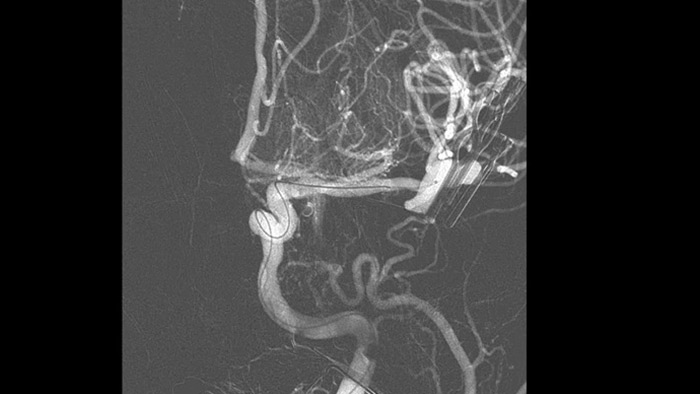

SmartCT Vaso IV

Comprobar la ubicación y la longitud del coágulo

SmartCT Vaso permite la visualización más allá del coágulo con imágenes periprocedimiento de las caras distales de los vasos en el accidente cerebrovascular isquémico. SmartCT Vaso es una técnica de adquisición basada en una TC de haz cónico y una inyección de contraste intrarterial. Permite la visualización más allá del coágulo con imágenes periprocedimiento de las caras distales de los vasos en el accidente cerebrovascular isquémico. Mediante el llenado retrógrado, se ven las estructuras de los vasos antes y después del coágulo. SmartCT Vaso 3D Roadmap puede utilizarse para visualizar los dispositivos de recuperación de coágulos.